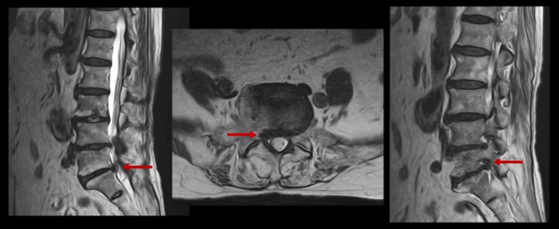

또 위로 올라가서 2번 3번 관절을 보면 왼쪽으로 디스크가 파열되어 위로 밀려 올라가있고

3번 4번 마디를 보면 왼쪽으로 디스크가 많이 밀려나와 있습니다.

이 두 마디가 왼쪽 증상, 특히 허벅지 통증을 일으키는 원인으로 보입니다. 이렇게 여러 마디가 안 좋을수록, 또 고령일수록 수술하기가 더 까다로워지는데 또 큰 문제는 이 환자분은 근감소증이 심하게 진행된 상태로, 여기 MRI에서 보시다시피 허리 하부의 기립근 근육이 전부 지방으로 변해버려 근육 자체가 거의 없는 상태인 것입니다.